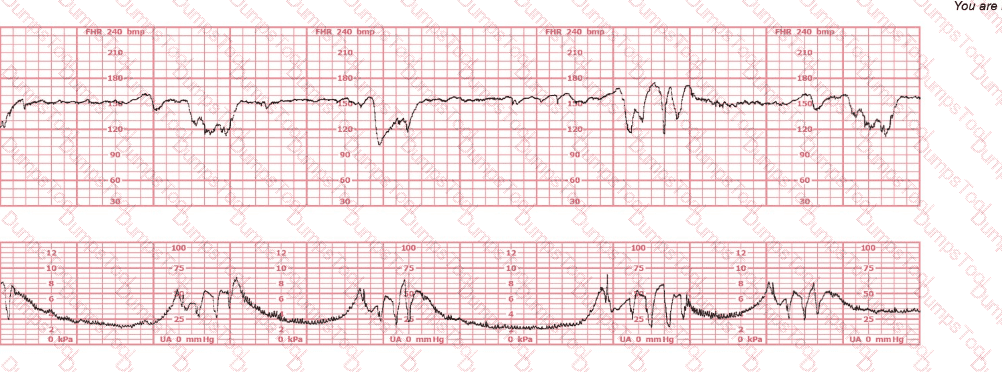

A woman at 39-weeks gestation is being induced. She has chronic hypertension controlled by methyldopa (Aldomet). Spontaneous rupture of membranes has occurred; she is 10 cm dilated and at +1 station. The fetal monitor tracing shown is obtained by spiral electrode and tocodynamometer. The next best appropriate action is to: